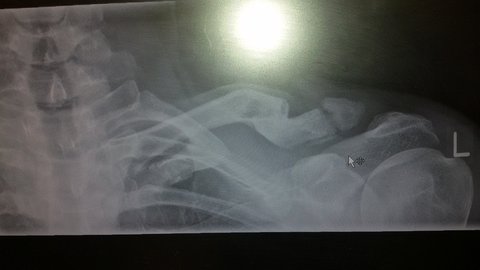

On the 4th fracture mine wouldn't heal. (Piece at the end in picture). There's just not enough blood supply in the bone anymore. Its been over 2 yrs now and it's ok. Doesn't really give me ant pain unless I fall on it then it's sore for a few weeks. I can still Mtb and ride MX but my shoulder isn't as good as it used to. But it's managable, the consultation said I'm less likely to break it again as there's float in it now. Not sure if thats good or bad Lol.

Due to the anaesthetic properties of the shock reflex I managed to pop the bit of my collarbone poking straight up out of my shoulder back into roughly the position it was before the break and that's where it still sits now:

Notperfect by any means, and it aches if I put weight on it for any length of time, but it hasn't affected my riding at all.